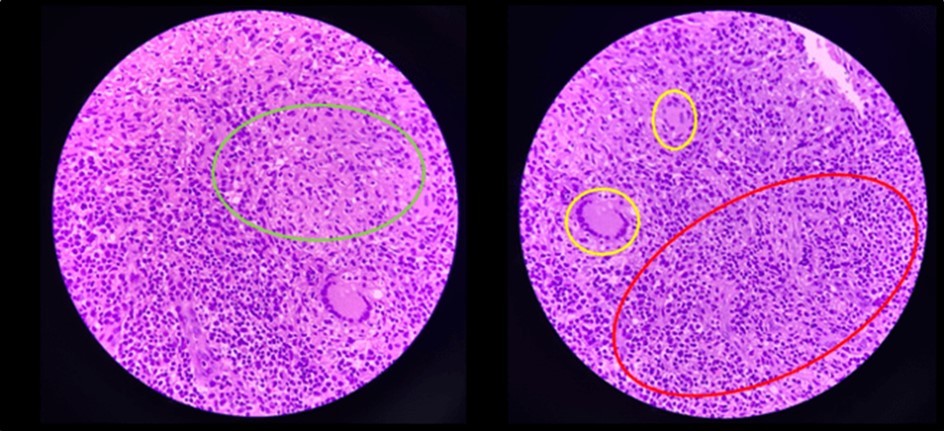

Figure 7.Pathologic slide in the high power field. Inside the green circle is the epitheloid histiocytes. The yellow circles are the Langhan’s type multinucleated gian cells. And inside the red circle is the lymphocytic infiltrates. Which is suggestive of tuberculous etiology.

Pathologic slide in the high power field. Inside the green circle is the epitheloid histiocytes. The yellow circles are the Langhan’s type multinucleated gian cells. And inside the red circle is the                        lymphocytic infiltrates. Which is suggestive of tuberculous etiology.